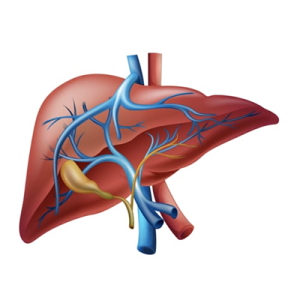

Liver Abscess and Cyst

Hepatocellular Carcinoma

Fatty Liver

Secondary Liver Cancer (Liver Metastases)

Non-Cancerous (Benign) Liver Tumours

Read MoreHPB – Liver

Treatment of liver tumors, cysts, and other conditions with precision...